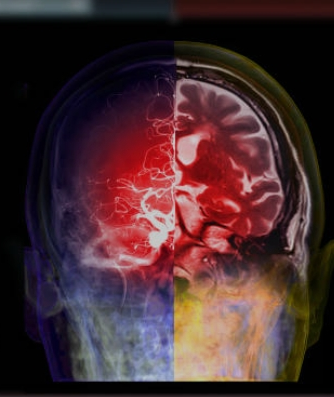

뇌졸중은 뇌혈관이 막히거나 터지는 상황에서 발생하는 질환으로, 뇌에 충분한 혈액이 공급되지 않아 발생합니다. 이는 뇌세포에 산소와 영양분을 제공하는 혈관의 문제로 인해 발생하며, 뇌 기능의 저하를 가져올 수 있습니다. 뇌졸중은 크게 뇌경색(허혈성 뇌졸중)과 뇌출혈로 나뉩니다. 뇌경색은 혈관이 막혀 발생하는 형태이며, 뇌출혈은 혈관이 터져 발생합니다. 두 형태 모두 신속한 치료가 필요하며, 예방을 위한 건강한 생활 습관 유지가 중요합니다. 특히 고혈압, 당뇨병, 고지혈증과 같은 위험 요소를 관리하는 것이 중요하며, 정기적인 건강 검진을 통해 이러한 위험 요소를 조기에 발견하고 관리해야 합니다.